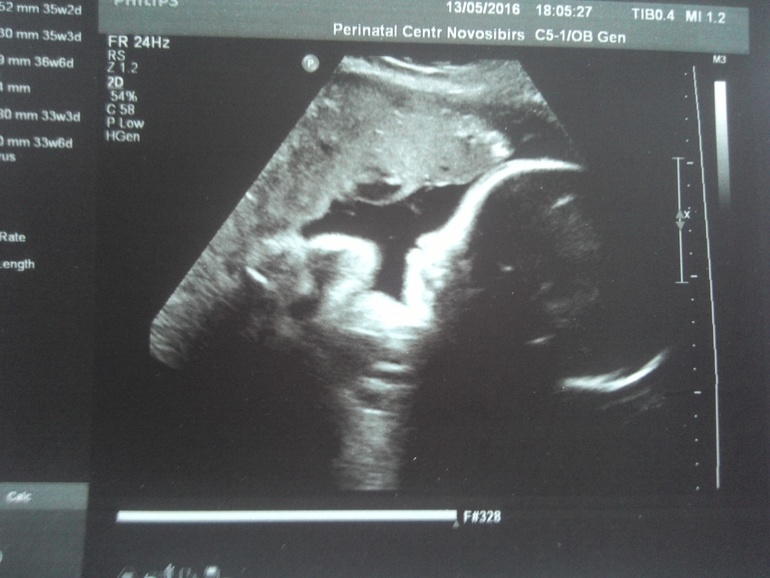

Ну и вот фото с узи))